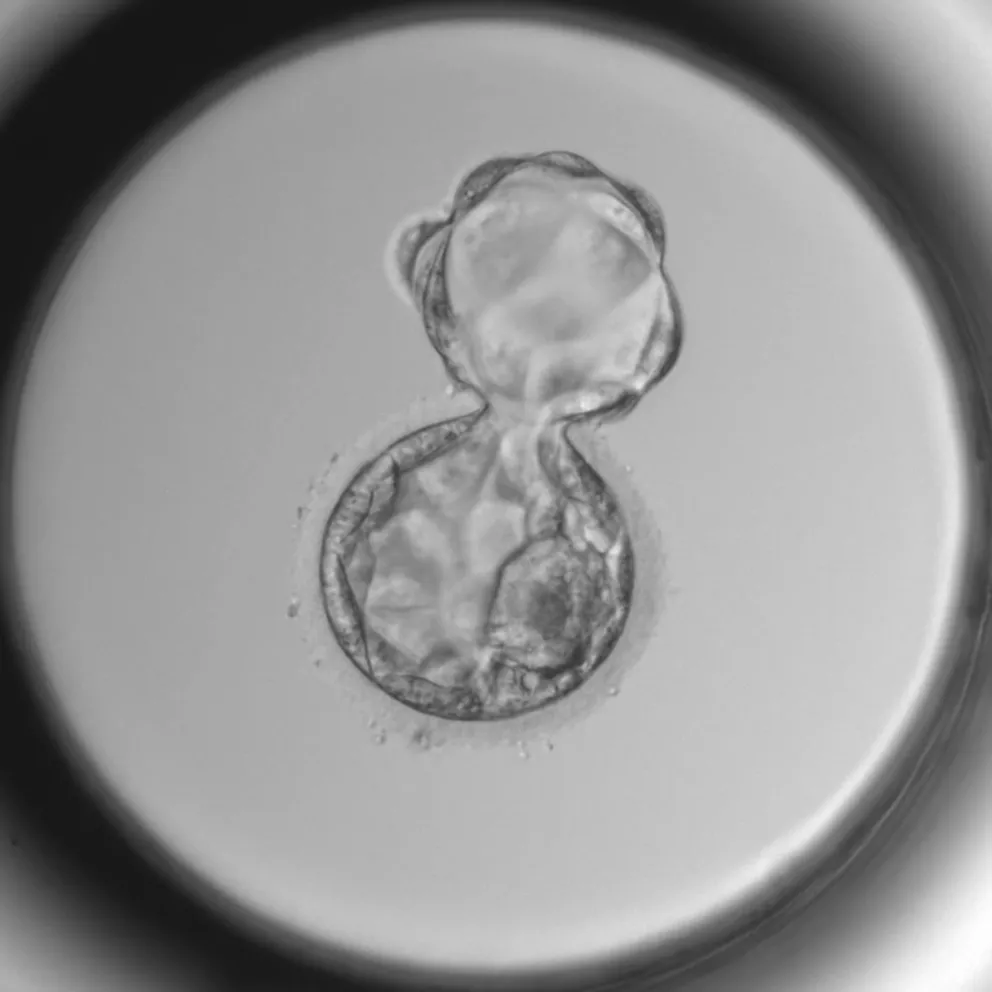

Embryo

Genetický screening jako prevence případných nezdarů

Další neméně důležitou metodou je genetický screening. „Ve věku nad 35 let například výrazně vzrůstá počet embryí s náhodnými změnami v počtu chromozomů, které můžeme vyloučit pomocí preimplantačního genetického screeningu. Tím urychlíme celý proces a můžeme předejít případným potratům,“ uzavírá Veronika Faměrová (na fotce níže).